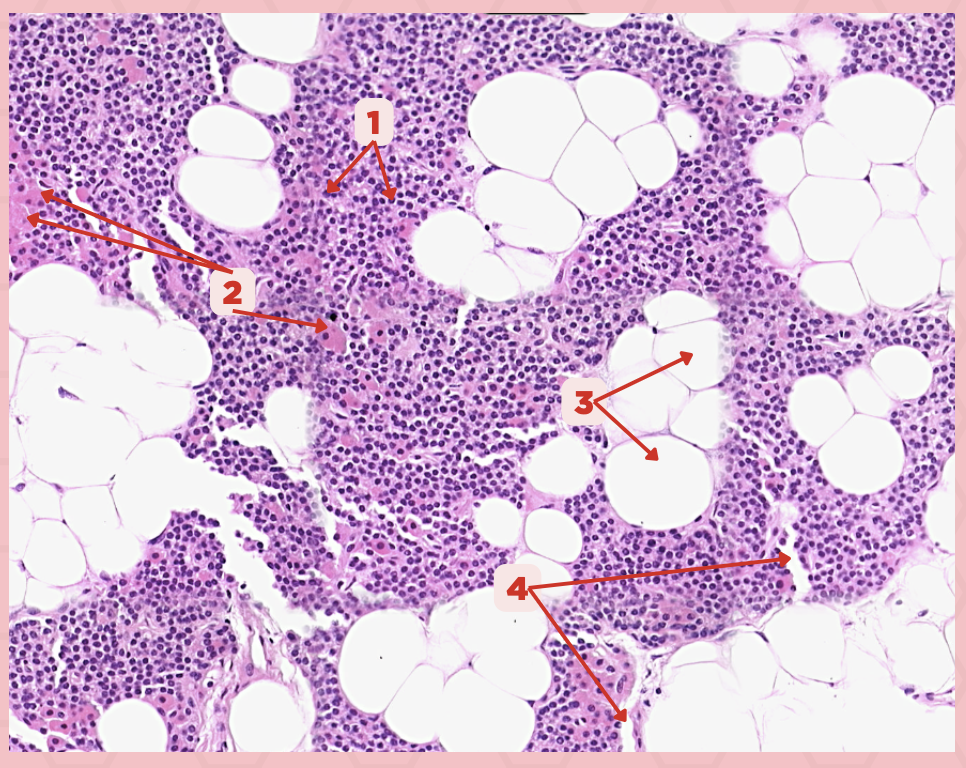

Parathyroid

Identify the specimen.

Chief Cells

Identify the specimen labeled as 1.

Oxyphil Cells

Identify the specimen labeled as 2.

Adipocytes

Identify the specimen labeled as 3.

Capillaries

Identify the specimen labeled as 4.

Newborns

Pointer #2 is hardly present in the parathyroid glands of _____.

Parathyroid

Identify the specimen.